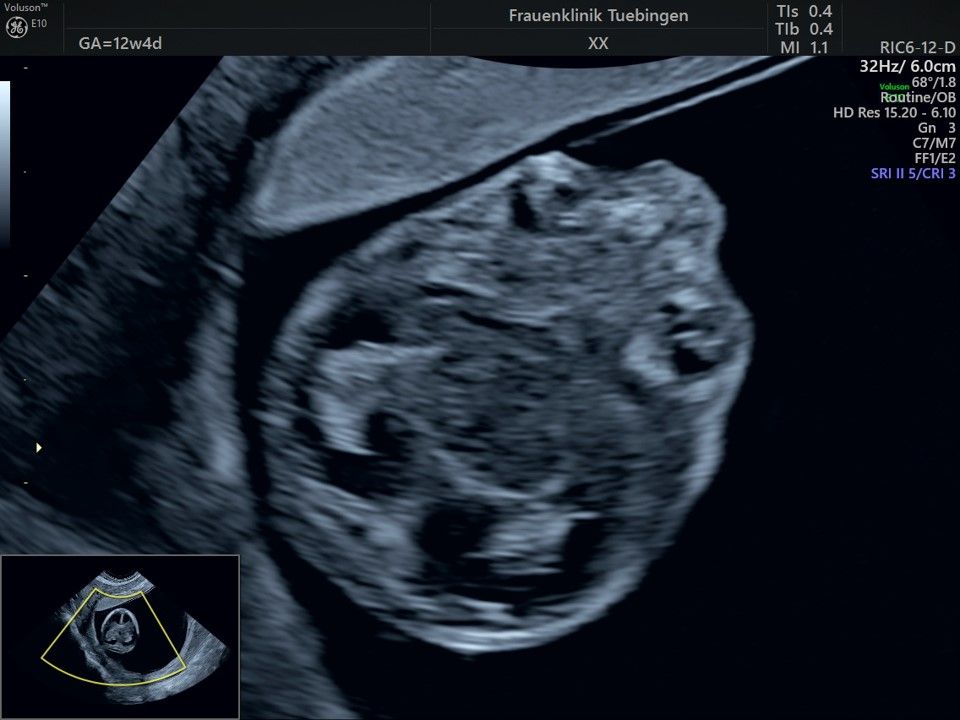

Im Rahmen des Ersttrimester-Screenings untersuchen wir die Organe des Feten mittels Ultraschall. Dabei machen wir auch gerne ein Bild für Sie.

Obwohl der Fet zu diesem Zeitpunkt erst zwischen 5 und 8cm groß ist, lassen sich bereits etwa die Hälfte aller schwerwiegenden Fehlbildungen erkennen bzw. ausschließen. Sollten wir eine Auffälligkeit sehen, werden wir mit Ihnen den Befund und das weitere Vorgehen ausführlich besprechen.

Die eigentliche Organuntersuchung findet um die 20.SSW (zweites Screening) statt. Das Ersttrimester-Screening und das zweite Screening sind sich ergänzende Untersuchungen und ersetzen sich gegenseitig nicht.